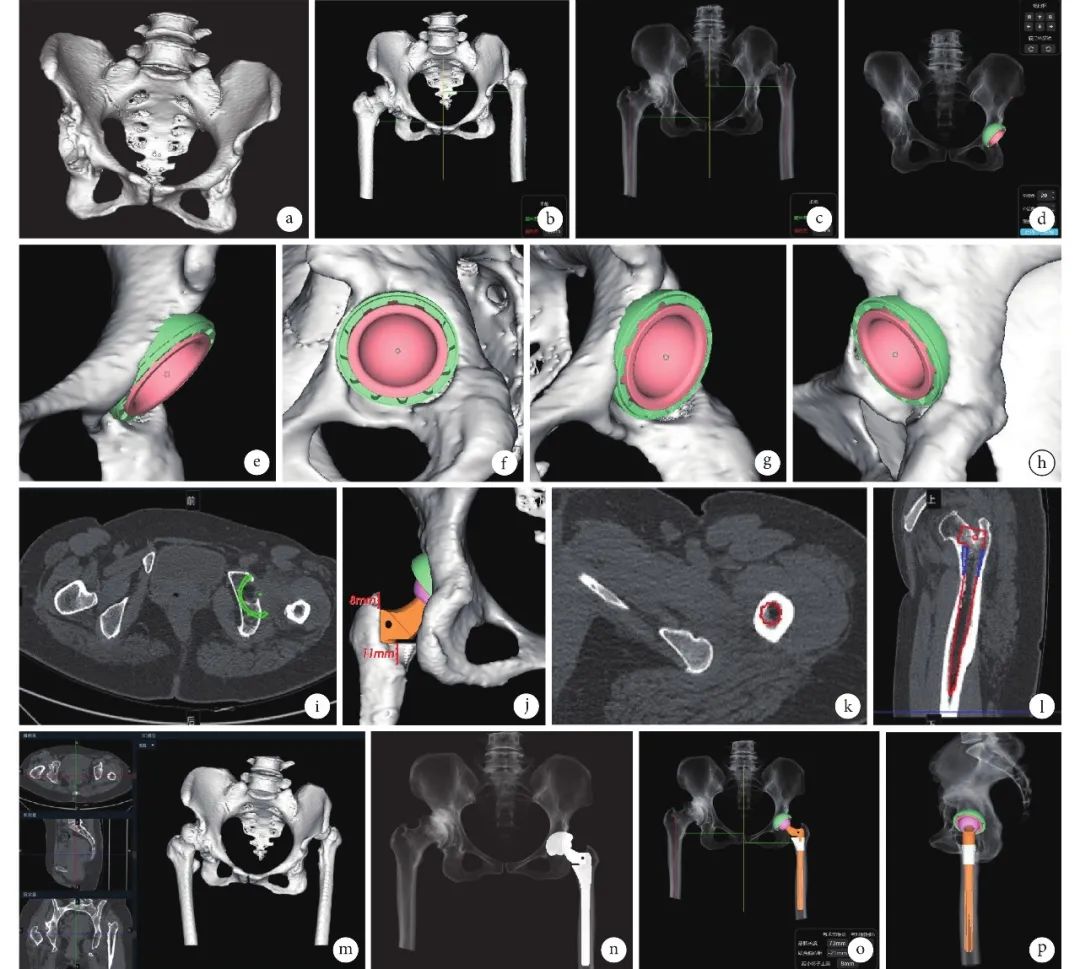

1 例术中发生股骨假体周围骨折,术中予以钢缆捆绑,术后 6 周助行器辅助下下地行走;其余患者均在术后 1 d 即采用助行器辅助下下地行走。本组手术时间 185~315 min,平均 239.43 min;住院时间 8~20 d,平均 9.96 d;脱离助行器时间 2~56 d,平均 5.09 d。术后患者均获随访 6 个月。患者切口均Ⅰ期愈合,无感染、脱位、再骨折、下肢深静脉血栓形成等并发症发生;术后 1 d 及 6 个月复查 X 线片示髋臼与股骨假体均固定牢靠且在安全范围;术后 1 d 双下肢长度差绝对值为(11.96± 13.48)mm,与术前比较差异无统计学意义(t=0.582,P=0.564)。术后 6 个月截骨均愈合良好。术后 1 周及 6 个月 Harris 评分分别为(69.5± 4.9)分和(79.2±5.7)分,手术前后各时间点间比较差异均有统计学意义(P<0.05)。术后 6 个月根据Harris 评分评价髋关节功能,获良 13 例、中 9 例、差 1 例。见图 5。

图 5 患者,女,52 岁,左髋 Crowe Ⅳ型、右髋 Crowe Ⅱ型 DDH,左髋先行 THA 联合 SSOT,术后 4 个月右髋行 THA 从左至右分别为双下肢站立位全长 X 线片、髋关节正位 X 线片及左髋关节侧位 X 线片 a. 术前;b. 术后 6 个月示髋臼侧与股骨侧假体固定均牢靠